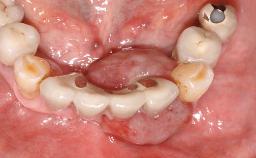

A 30-year-old female patient was referred to the Department of Periodontology of the University of Bern, Switzerland, by a dentist in private practice. Tooth 45 had been congenitally missing and had been replaced with a titanium implant three years prior to the first visit at the Department of Periodontology. The tissue level implant had a diameter of 4.1 mm, a length of 12 mm, and a sandblasted and acid-etched (SLA) surface (Straumann® Dental Implant System; Institut Straumann AG, Basel, Switzerland). The metal-ceramic crown on implant 45 had been cemented permanently. Implant 45 had been diagnosed with peri-implantitis by the referring dentist in the course of regular supportive care.